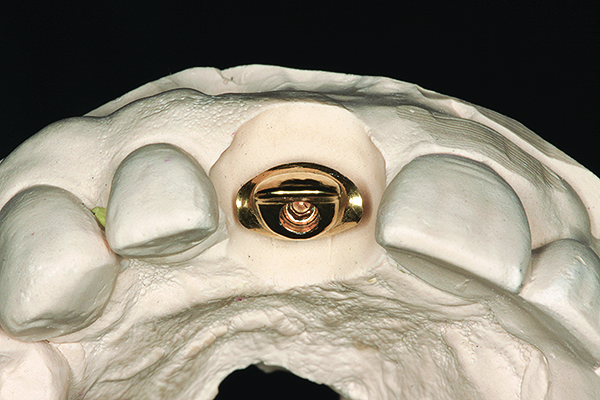

The implant impression, along with a cast of the opposing arch and shade, were sent to a commercial dental laboratory for fabrication of a master cast. A signed work order and the master cast were then sent to the BellaTek® Production Center (BIOMET 3i) for a lab-designed abutment (LDA) (Figure 14). A BellaTek® abutment was milled from a solid blank of titanium, and a gold-colored titanium-nitride coating was applied to impart a warm color through the thin marginal peri-implant tissues.

Fig 15. The master cast and definitive titanium-nitride–coated abutment.